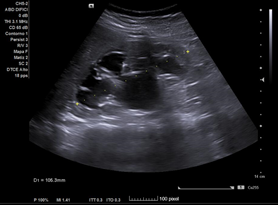

En ecografía clínica desde el centro de salud, se objetiva gran dilatación del sistema excretor del riñón derecho, con adelgazamiento de la cortical (hidronefrosis grado III-IV). No se aprecia litiasis u otra causa obstructiva a nivel renoureteral ni vesical. Riñón derecho conserva tamaño normal. Riñón izquierdo de tamaño y ecoestructura normales, sin dilatación piélica. Vejiga bien replecionada sin alteraciones en su pared.

Concordancia con el hospital. Se realiza Urografía por Tomografía Computada que confirma hidronefrosis grado IV en riñón derecho; no se objetivan litiasis renoureterales; se aprecia arteria accesoria polar inferior de dicho riñón, la cual cruza la unión pieloureteral ipsilateral.